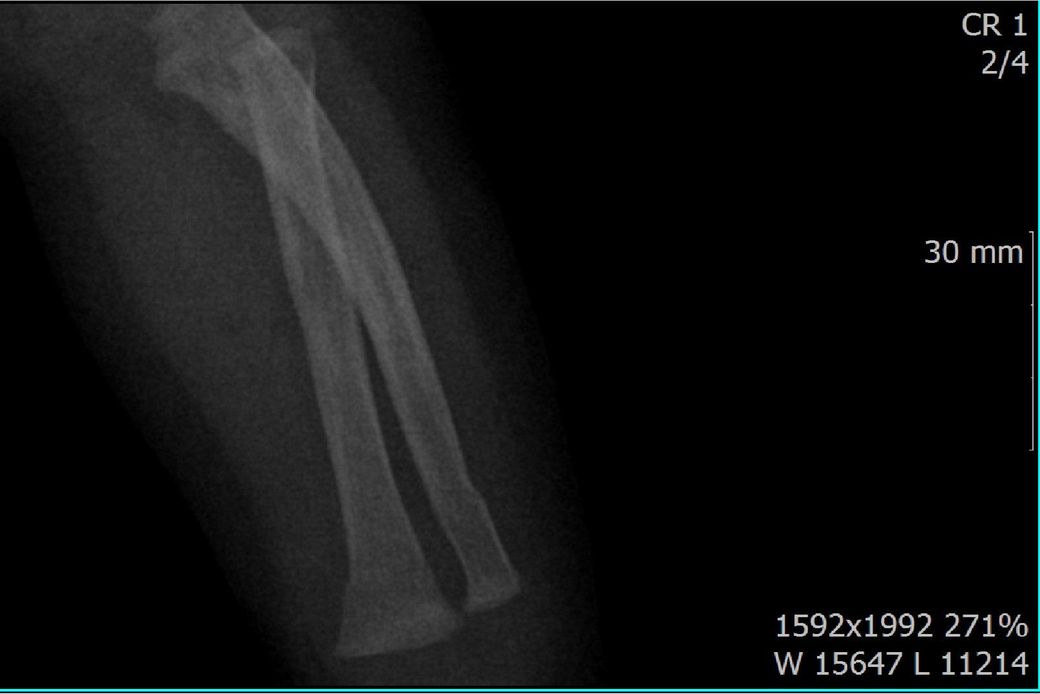

x ray 팔 골절 시기 추정해보고 싶습니다.

다름이 아니라, 첨부드린 엑스레이(X-ray) 사진처럼 골절 사실을 알게 되고 골절 발생 시점 대략적으로나마 추정시기를 파악하려고 문의 드리게 되었습니다

1) 3월 30일 촬영한 X-ray만으로 정확한 골절 시기를 100% 특정하는 데에는 한계가 있다는 점 충분히 인지하고 있기에 촬영날짜 기준으로 대략적으로 어느정도 시점에서 발생되었을 것으로 추측(ex 당일, 7~10일전, 7~14일 전, 10일 ~ 20일전, 14일 ~ 30일전 등등등)되는지 이해하고 싶습니다.

• 2번 째 사진